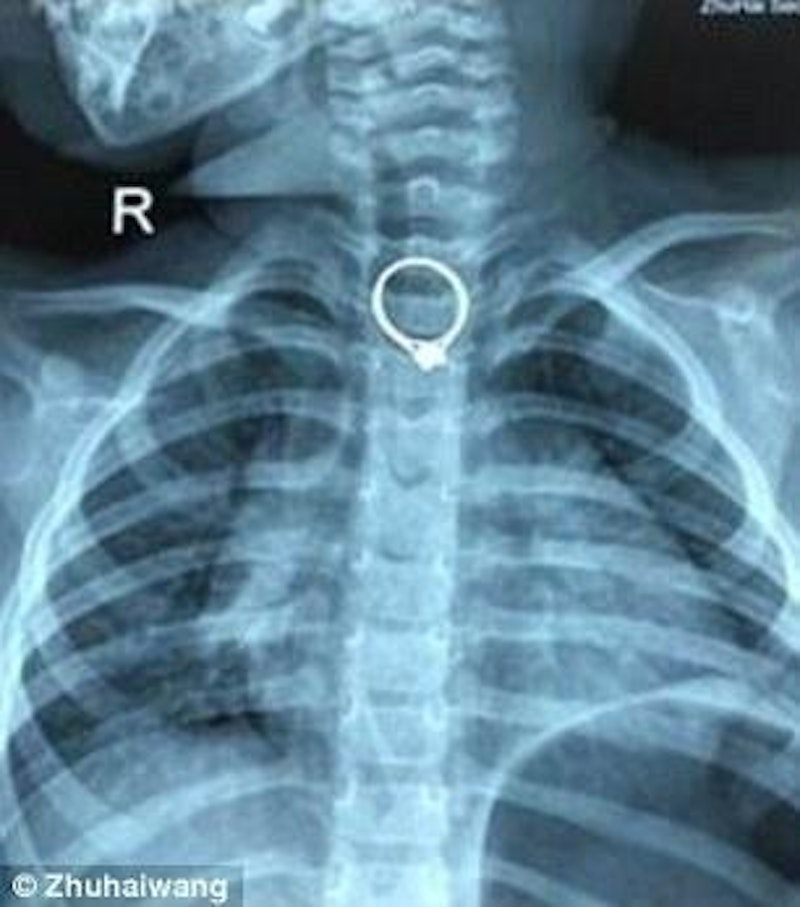

Auf Röntgenbilder wurde der Ring entdeckt

Sofort fuhr die Frau mit dem kleinen Mädchen in die Klinik. Das Mädchen wurde sofort ins Röngten geschickt – auf den Bildern war deutlich der Diamantring zu erkennen, der in Beibeis Hals steckte.